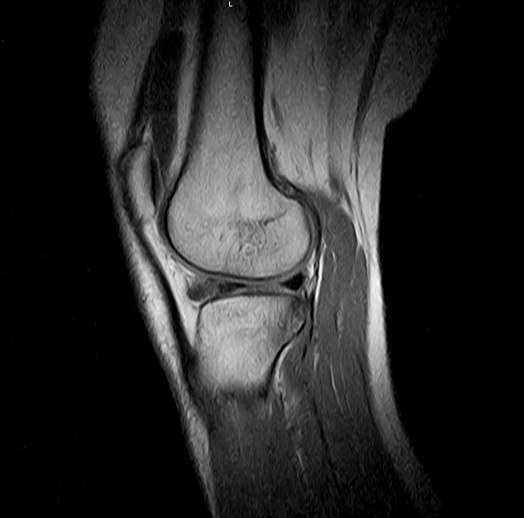

To understand what’s behind knee pain, it’s important to grasp the anatomy of the knee. There are five separate components:

1. Bone. The tibia (shin bone), femur (thigh bone), and patella (kneecap) form the knee.

2. Cartilage. The ends of each bone are covered by cartilage that functions as a protective layer and shock absorber.

3. Muscles. Two muscle groups support the knee: the quadriceps at the front of the thigh, and the hamstring, at the back.

4. Tendons. Muscles are connected to bones through tendons.

5. Ligaments. Ligaments connect bones to one another. They have different functions in the knee, like limiting movement and protecting the joints.

• Injury. These include ACL tears, fractures, torn meniscus, bursitis, and tendinitis.